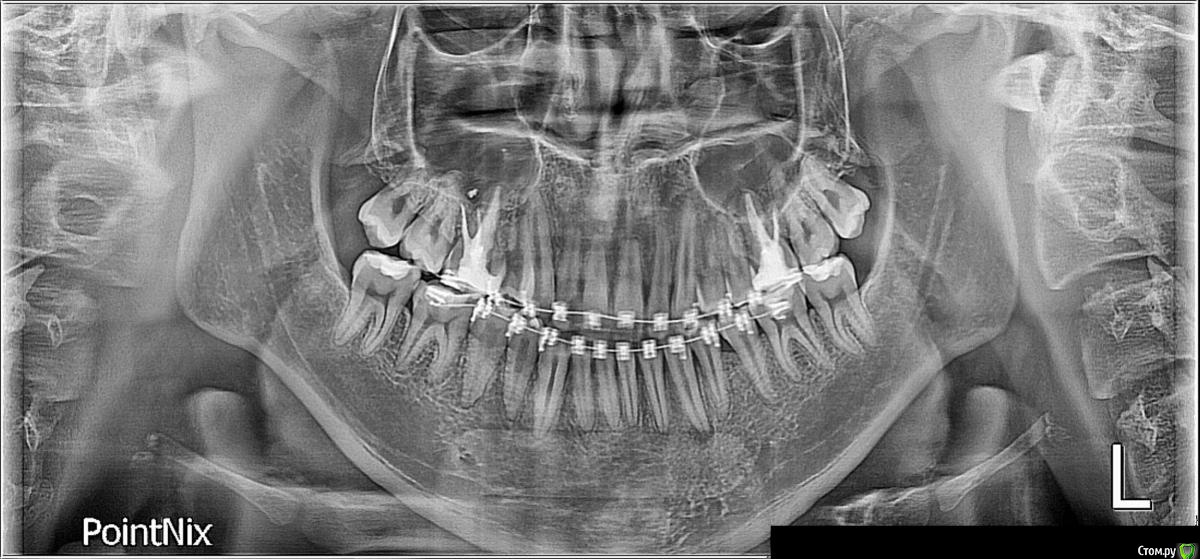

f0stung Опубликовано 20 июня, 2018 Поделиться Опубликовано 20 июня, 2018 М. 20л, нахожусь на ортодонт. лечении. Вырвали 14, 38, 48 зубы. Сейчас стоит вопрос на удалении 18 и 28.Специалисты напишите ваше мнение.Заранее благодарю Ссылка на комментарий